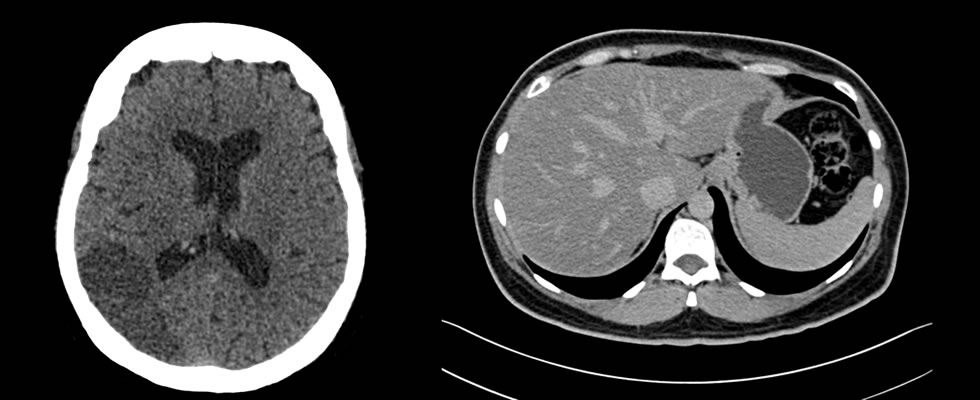

Interpretación de Estudios de Tomografía Multicorte

La interpretación de estos estudios es realizado en estaciones de trabajo que funcionan bajo una plataforma basada en tecnología Apple y el software OSIRIX, que garantiza las herramientas necesarias para la adecuada interpretación de los estudios en las diferentes modalidades, incluyendo los de tomografía multicorte con reconstrucciones en 2D Y 3D. El grupo de médicos Radiólogos encargados de la lectura de tomografías tienen entrenamiento en el área con experiencia laboral en reconocidas instituciones de la ciudad de Cali.